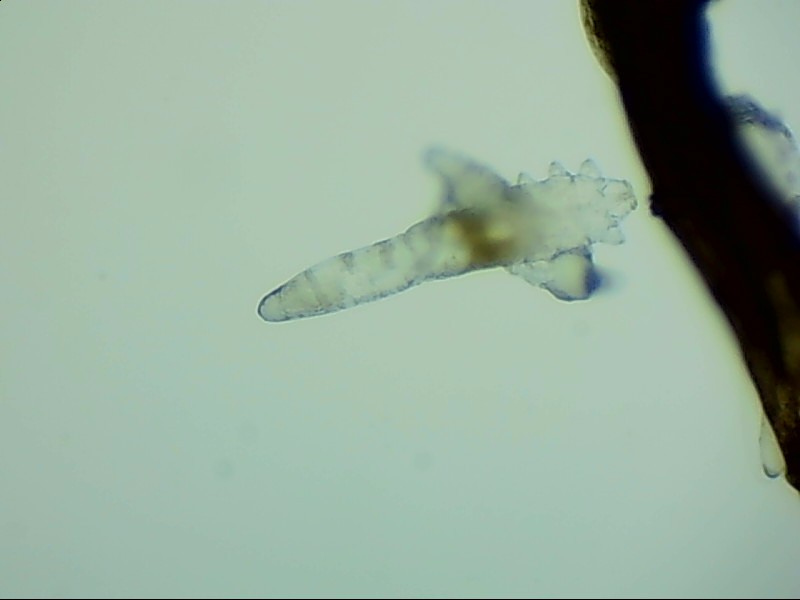

蠕形螨:

人體上寄生著兩種蠕形螨,分別是毛囊蠕形螨和皮脂蠕形螨,它們以睫毛囊上皮細(xì)胞、腺體內(nèi)脂質(zhì)為食物,因此主要寄生在面部、眼睛、頭皮等地方,其中寄生在眼睛里的蠕形螨主要活動在睫毛毛囊、睫毛皮脂腺,以及瞼板腺里。

蠕形螨完全長大也只有0.1-0.2毫米,因此肉眼難以看到它們,只有在電子顯微鏡下我們才能看到睫毛根部的一只只蠕形螨。這些螨蟲每天都很活躍,且繁殖速度極快,完成一代生活史僅需大概15天。

螨蟲無所遁形,螨蟲鏡檢:

螨蟲鏡檢主要是通過顯微鏡觀察,它能無死角放大你的睫毛,讓螨蟲無處可躲。

在檢查的時候,醫(yī)生要在每個眼瞼上拔出幾根比較典型的睫毛,然后放在光學(xué)顯微鏡下,尋找有沒有螨蟲,同時觀察螨蟲的數(shù)量多少。

如果任意一個眼瞼上螨蟲數(shù)量較多,再加上你的眼睛有局部癥狀,后續(xù)就需要進(jìn)行相應(yīng)的治療了。